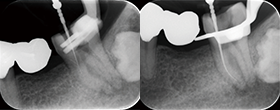

Case2 直線根管

• CC「左下奥違和感」主訴に来院

左下6遠心根に透過像認める

• インレー除去

透過像に一致した部位にサイナストラクト認める

• コンポジットレジンにて隔壁作成

• 作業長確認

最終拡大#30/.04テーパー